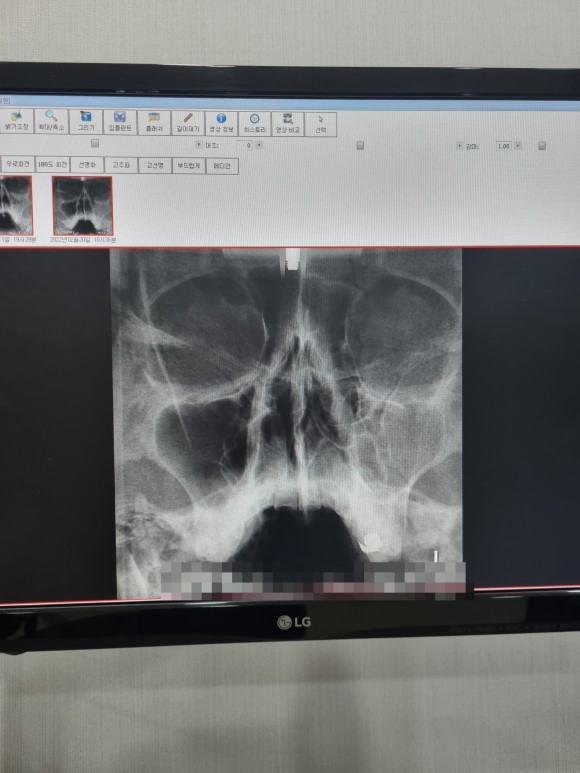

부비강염

사진은 좌우 반전되어 있고 사진의 오른쪽이 실제 얼굴상 왼쪽이다.)

좌우 차이가 보이나요?

시커멓게 비어 있는 것이 정상인데 반대편은 희고 뭔가 가득 차 있다

이 가운데 코뼈가 약간 구부러져 있다는 얘기도 들었다.생전에 몰랐던 것은 있지만 지장은 없다고 해서 그냥 살라고 했다.